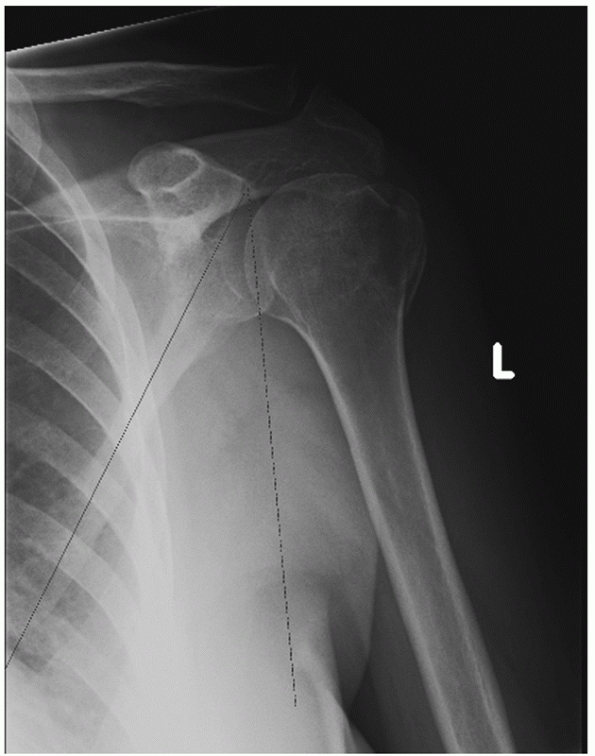

displacement of the distal fragment resulting in a change in the

contour of the affected shoulder, the so-called drooping shoulder (Fig. 37-17). Apart from this possible caudal and rotational displacement, it is also suggested, although criticized by some,129,175 that the glenoid fragment is displaced anteromedially by contraction of the rotator cuff muscles (Fig. 37-18).46,66,71

FIGURE 37-17 Drooping aspect of the left shoulder.

FIGURE 37-18 A,B. Radiographs of an ipsilateral scapular neck and midshaft clavicle fracture. C. The glenoid fossa is still not reduced despite open reduction and internal fixation of the clavicle.